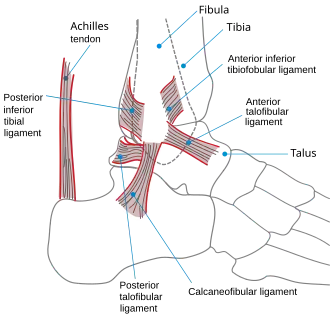

The ankle region refers to where the leg meets the foot (talocrural region).[5] The ankle joint is a highly constrained, complex hinge joint composed of three bones: the tibia, the fibula, and the talus.[6][7] The weight-bearing aspect of the tibia closest to the foot (known as the plafond) connects with the talus. This articulation (where two bones meet) is primarily responsible for plantarflexion (moving your foot down) and dorsiflexion (moving your foot up).[7] Together the tibia and fibula form a bracket-shaped socket known as the mortise, into which the dome-shaped talus fits.[8] The talus and the fibula are connected by a strong group of ligaments, which provide support for the lateral aspect of the ankle. These ligaments include the anterior talofibular ligament (ATFL) and the posterior talofibular ligament (PTFL).[9] The calcaneofibular ligament (CFL), which connects the fibula to the calcaneus, or heel bone, also provides lateral support. The deltoid ligament provides support to the medial part of the ankle (closest to the midline). It prevents the foot from excessively everting, or turning outwards while also preventing the talus from externally rotating.[9] The distal parts of the tibia and fibula are connected by a connective tissue network referred to as the syndesmosis, which consists of four ligaments and the interosseous membrane.[9]